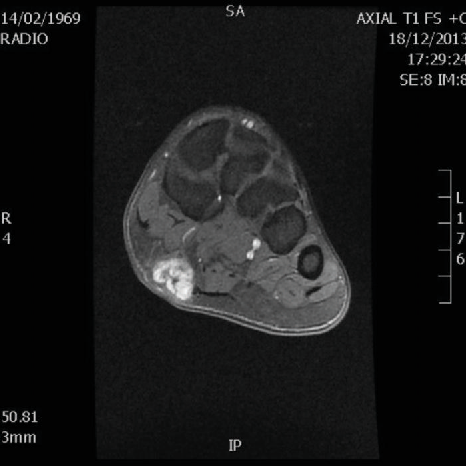

초음파 검사에서

발바닥 근막 섬유종은

저에코/동등에코의 결절이 보이고

발바닥 근막과 연결성이 확인됩니다.

초음파 검사나 MRI 검사로

확인 가능하고,

X-ray에서는 확인하기 어려워

족저근막염으로 오해하기 쉽습니다.